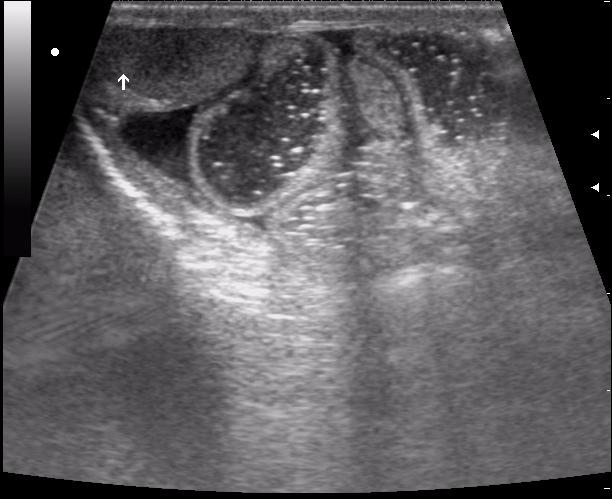

(девушке 23 года. фиброматоз матки)

ещё раз - это матка 23-летней девушки. то есть, ВСЁ это, то что Вы видите, да-да, на весь экран - это матка.

Диагноз - фиброматоз. направлена строго на север и налево. к соседям. (онкодиспансер)

ну вот куда здесь ставить бодимаркер и какой?